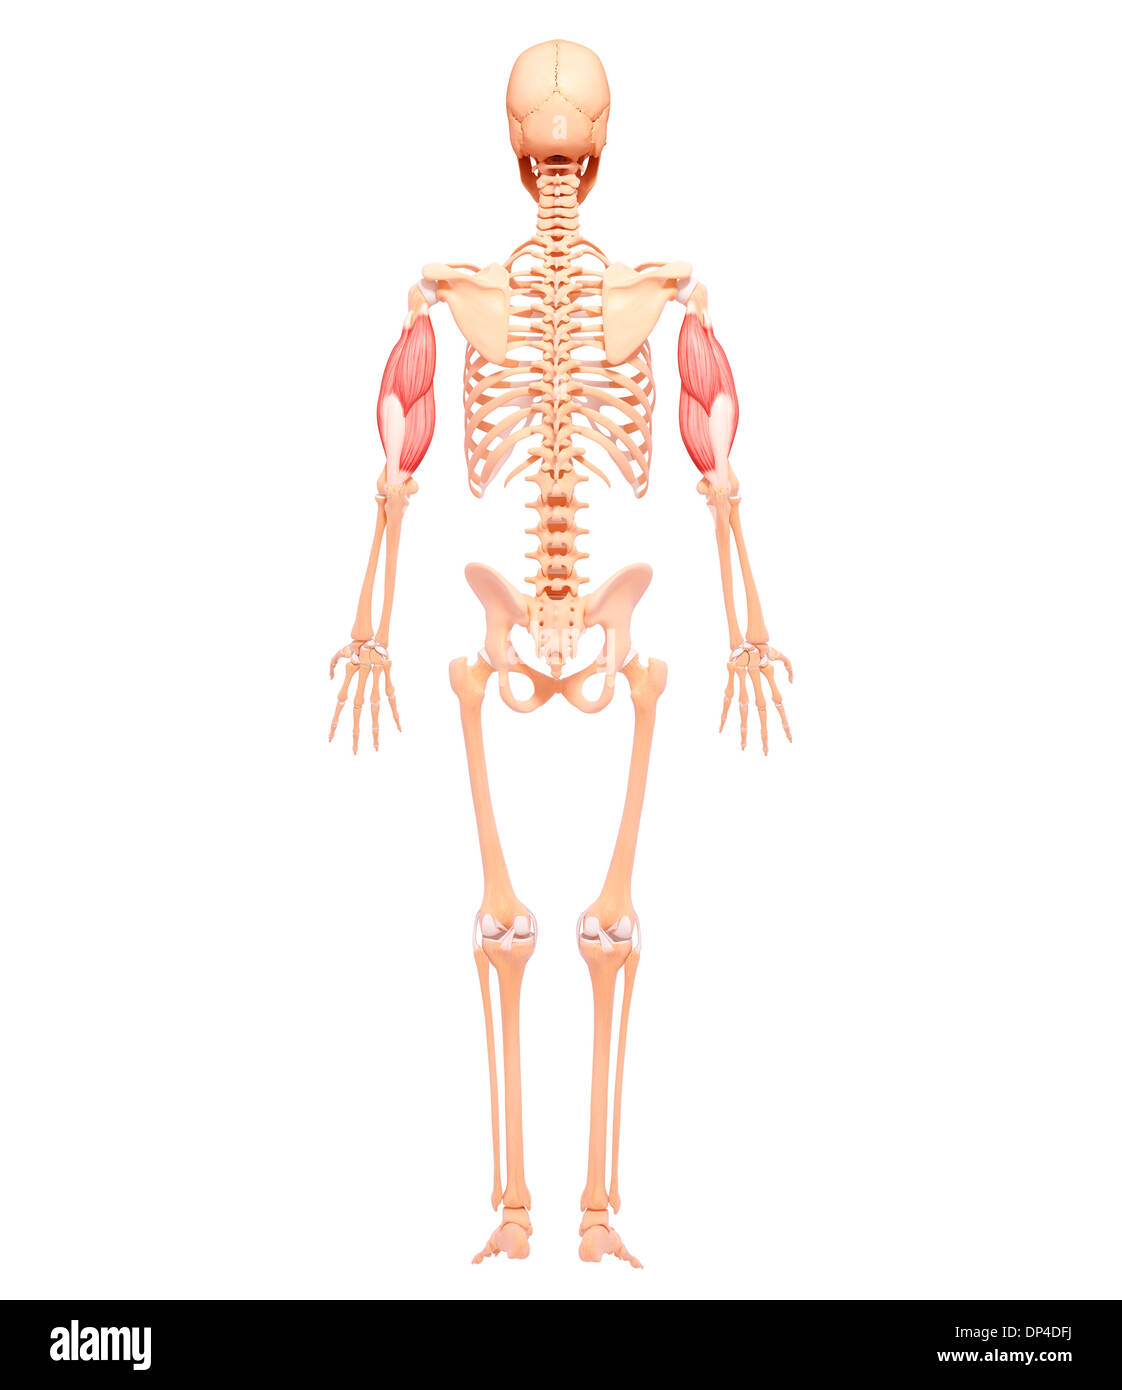

Human Skeleton, artwork Banque D'Imageshttps://www.alamyimages.fr/image-license-details/?v=1https://www.alamyimages.fr/human-skeleton-artwork-image65257618.html

Human Skeleton, artwork Banque D'Imageshttps://www.alamyimages.fr/image-license-details/?v=1https://www.alamyimages.fr/human-skeleton-artwork-image65257618.htmlRFDP4MN6–Human Skeleton, artwork